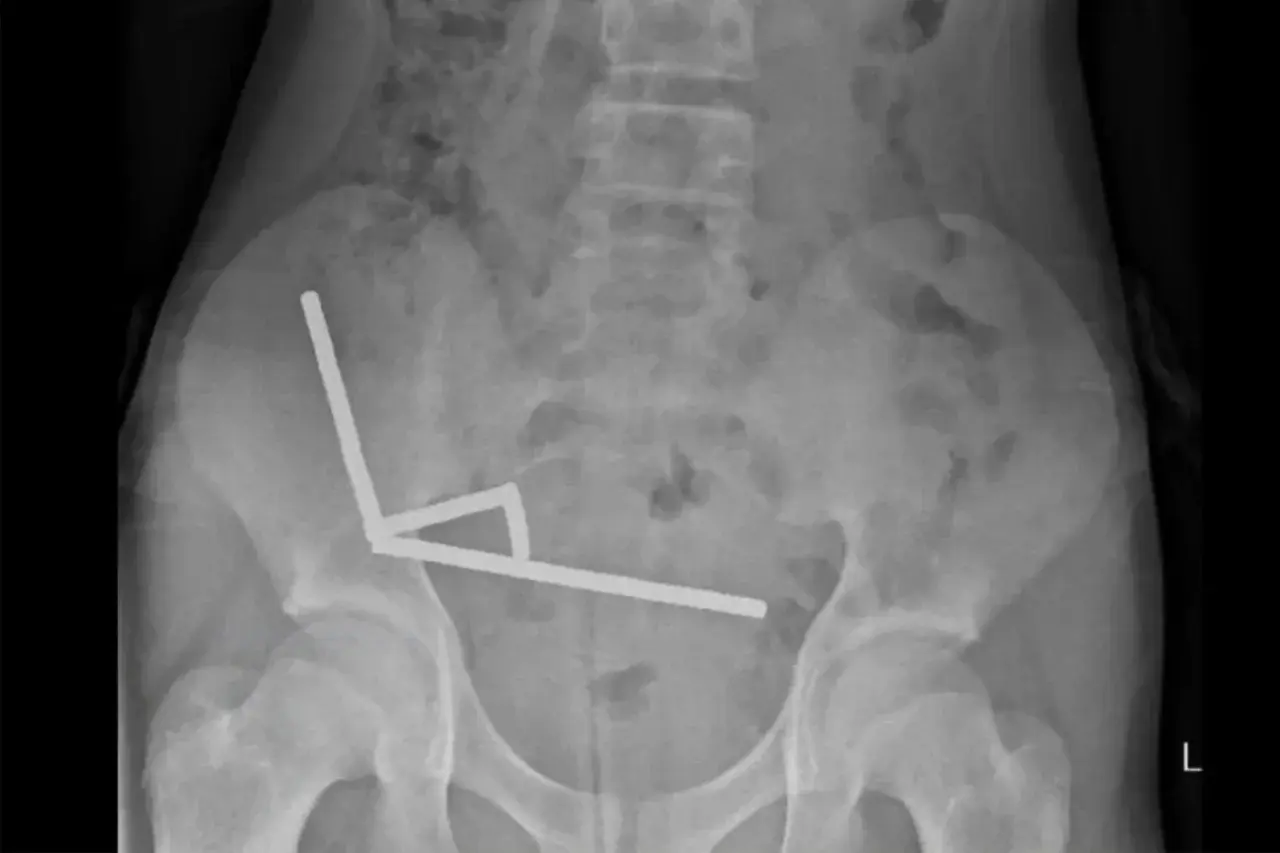

ซึ่งแพทย์ต้องตกใจเมื่อพบว่า แม่เหล็กแรงสูงในลำไส้ของเขา ดูดกันและกันและก่อตัวเป็นสายยาว 4 เส้น ส่งผลทำให้เกิดภาวะเนื้อตายหลายจุด ในลำไส้เล็กและลำไส้ใหญ่ส่วนต้น และ ในที่สุดเขาต้องเข้ารับการผ่าตัดฉุกเฉิน เพื่อช่วยชีวิตของเขา โดยแพทย์ได้ผ่าตัดนำลำไส้บางส่วนออก...

รายงานในวารสารการแพทย์นิวซีแลนด์ ระบุว่า "เด็กชายคนนี้ กล่าวว่า "เมื่อสัปดาห์ก่อน เขาได้กลืนแม่เหล็กนีโอไดเมียม ไปประมาณ 80-100 ชิ้น แต่ละชิ้นมีขนาดเพียง 5 มม.x2 มม. ถึงแม้ว่านิวซีแลนด์จะห้ามจำหน่ายแม่เหล็กแรงสูง ที่มีขนาดเล็กในปี 2013 แต่แม่เหล็กเหล่านี้ยังคงหาซื้อได้ง่าย ผ่านแพลตฟอร์มอีคอมเมิร์ซข้ามพรมแดน โดยแพทย์อธิบายว่า "แม่เหล็กเหล่านี้ดึงดูดกันที่ตำแหน่งต่างๆในร่างกาย ส่งผลให้ผนังลำไส้ถูกกดทับ และ ทำให้เกิดภาวะเนื้อตายและทะลุ" โดยศัลยแพทย์ได้ทำการผ่าตัดฉุกเฉิน เพื่อนำแม่เหล็กออกทั้งหมด และ ตัดส่วนลำไส้ที่เสียหายออก หลังจากนั้น เด็กชายได้รับอนุญาตให้กลับบ้านได้ หลังจากผ่านไป 8 วัน